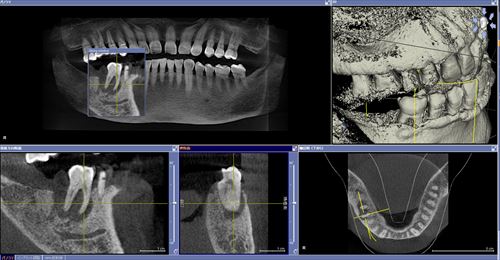

こんな状態でした。一番奥に膿の塊が見えます。歯周病と混在している病巣でぼくらの業界では治すのは難しいとされている1つの状態です。

術後2ヶ月CT。うん、いい!